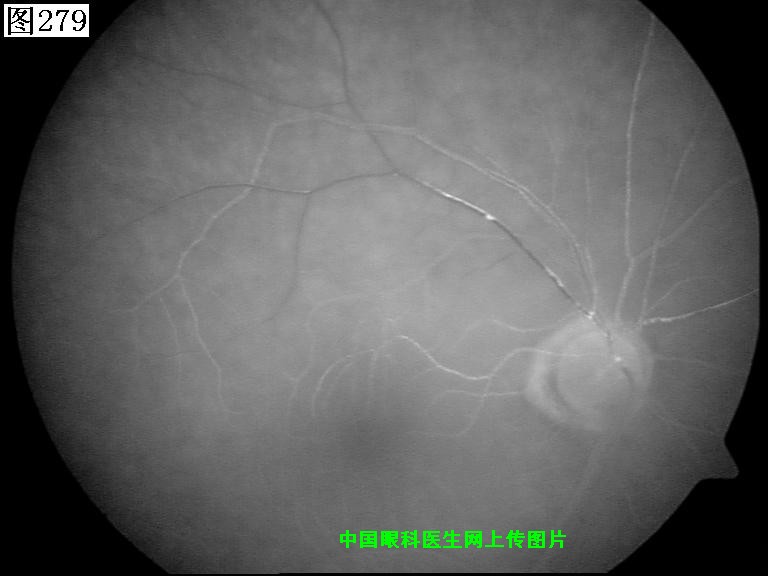

277 278 279 280